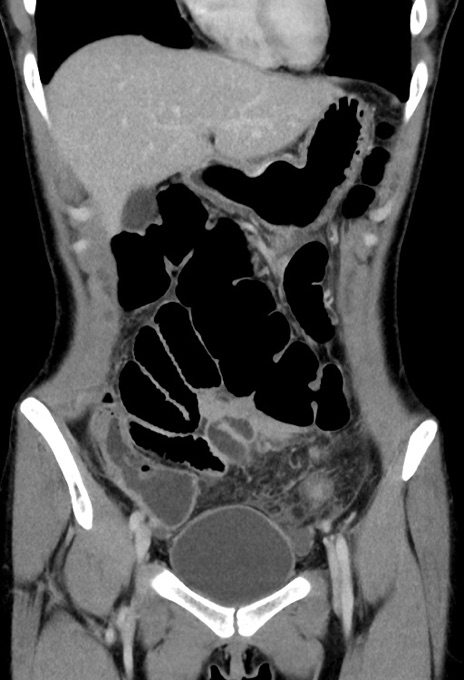

症例17(冠状断像)

【症例】20歳代女性

【主訴】嘔吐、下腹部痛

【現病歴】昨日夕食後に嘔吐し下腹部痛が出現。本日になっても嘔吐持続し改善しないため来院。

【身体所見】意識清明、BT 37.2℃、BP 108/67mmHg、腹部:平坦、やや硬、下腹部正中から右にかけて圧痛あり、反跳痛軽度あり、tapping pain(+)。

【データ】WBC 13600、CRP 14.94

横断像